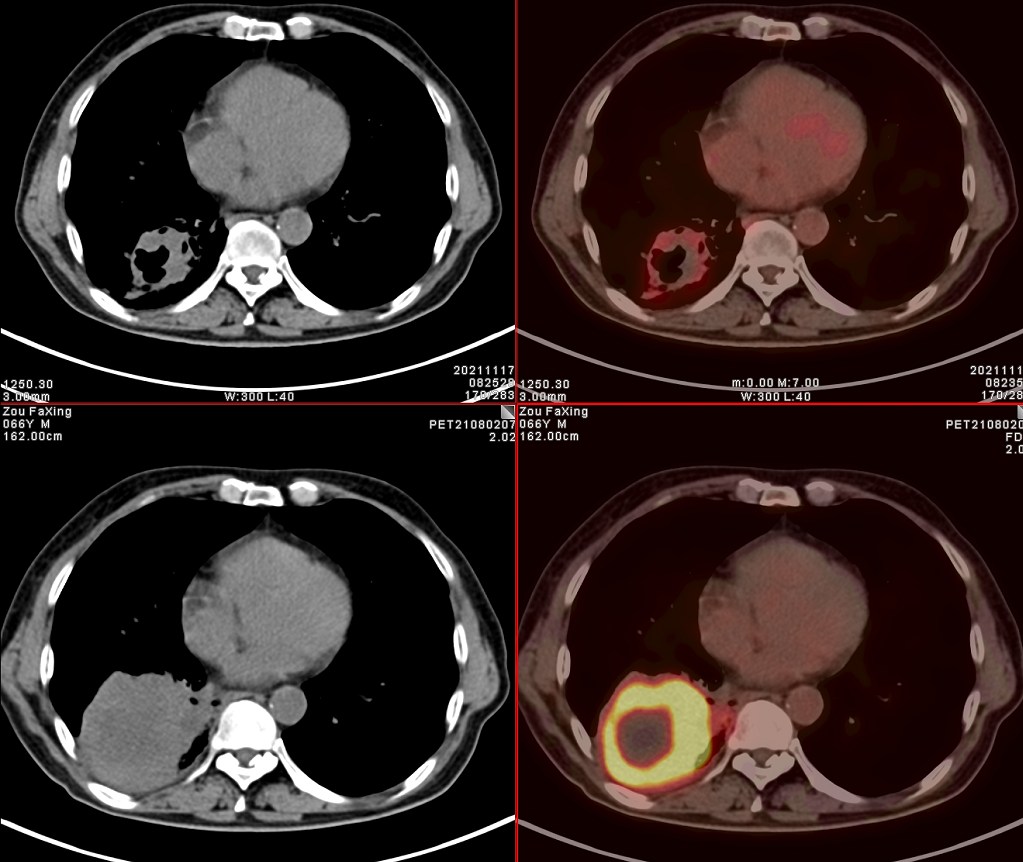

依据影像学分期,该患者后续进行了综合治疗:免疫+化疗+靶向治疗,其中化疗3期,免疫治疗2期及靶向治疗。3个月后患者再次进行了PET/CT检查,对治疗效果进行了评估。2021年11月PET/CT检查结果:

肿瘤病灶明显缩小、实性成分明显减少,肿瘤FDG代谢明显减低,相邻胸膜浸润明显改善,已经没有胸水征象。另外,全身其他部位未见明确转移性病变。

上面两张为治疗后,下面为治疗前

复查后PET/CT诊断:右肺下肺癌综合治疗后,肿瘤病灶明显缩小,FDG代谢明显减低,相邻胸膜未见高代谢病变,考虑肿瘤治疗后疗效显著,仅少量肿瘤活性残留。